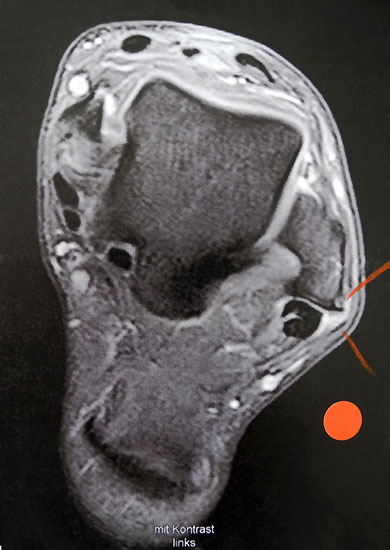

MRT mit KM bei Split der Peronaeus brevis Sehne in Höhe der Fibulaspitze

Abbildung 13

Klassischerweise beginnt eine Peronealsehnenruptur mit einem Distorsionstrauma. Bei dieser Verletzung kommt es zunächst zu einer Längsruptur (Peroneus-Split) der Peronaeus brevis Sehne in Höhe der Fibulaspitze. Bestehen nun Risikofaktoren wie eine persistierende Instabilität des Sprunggelenks oder ein bis zu diesem Zeitpunkt asymptomatischer Rückfußvarus, kommt bei jeder weiteren Distorsion zu einer Zunahme des Sehnenschadens bis hin zur vollständigen Kontinuitätsunterbrechung 38. Für das Peronaeus Split Syndrom gibt es kein klassisches Leitsymptom. Wichtig ist bei anhaltenden Beschwerden nach einem Distorsionstrauma an diese Differentialdiagnose zu denken und ein MRT mit Kontrastmittel zu veranlassen 39.